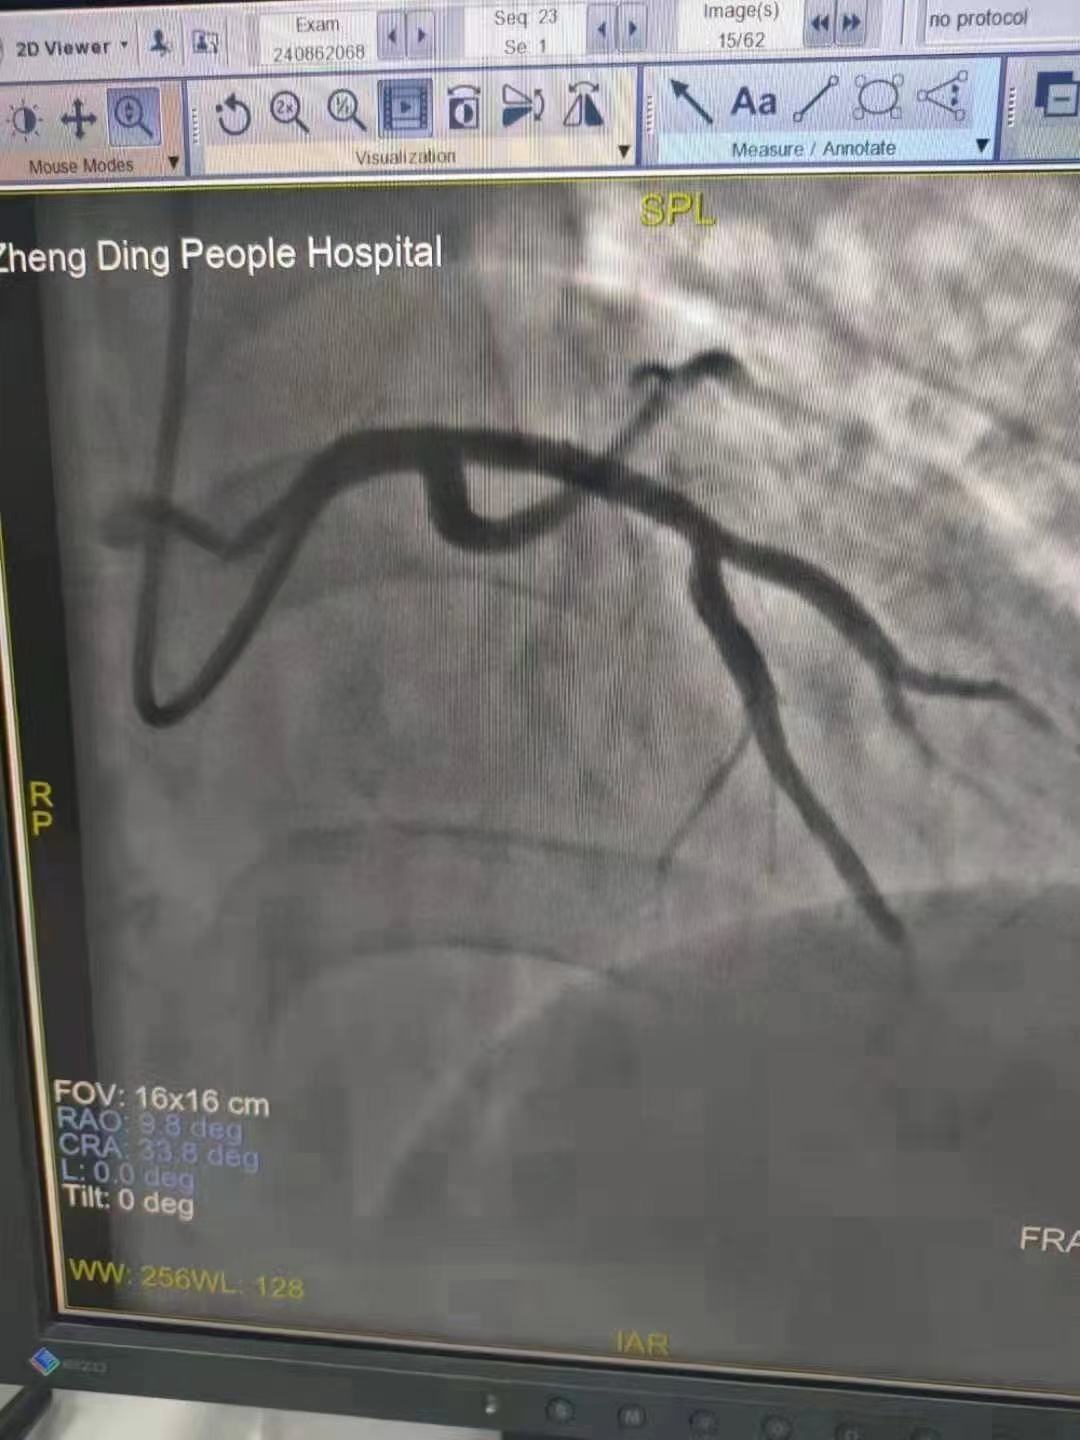

祝賀 正定縣醫(yī)院李京芳 主任團(tuán)隊(duì)成功為患者植入Xinsorb生物可吸收支架!